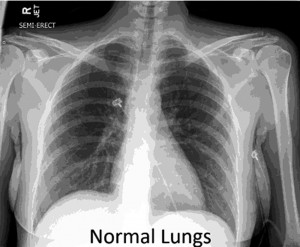

A Beautiful Lung X-Ray! | trumpetlungs